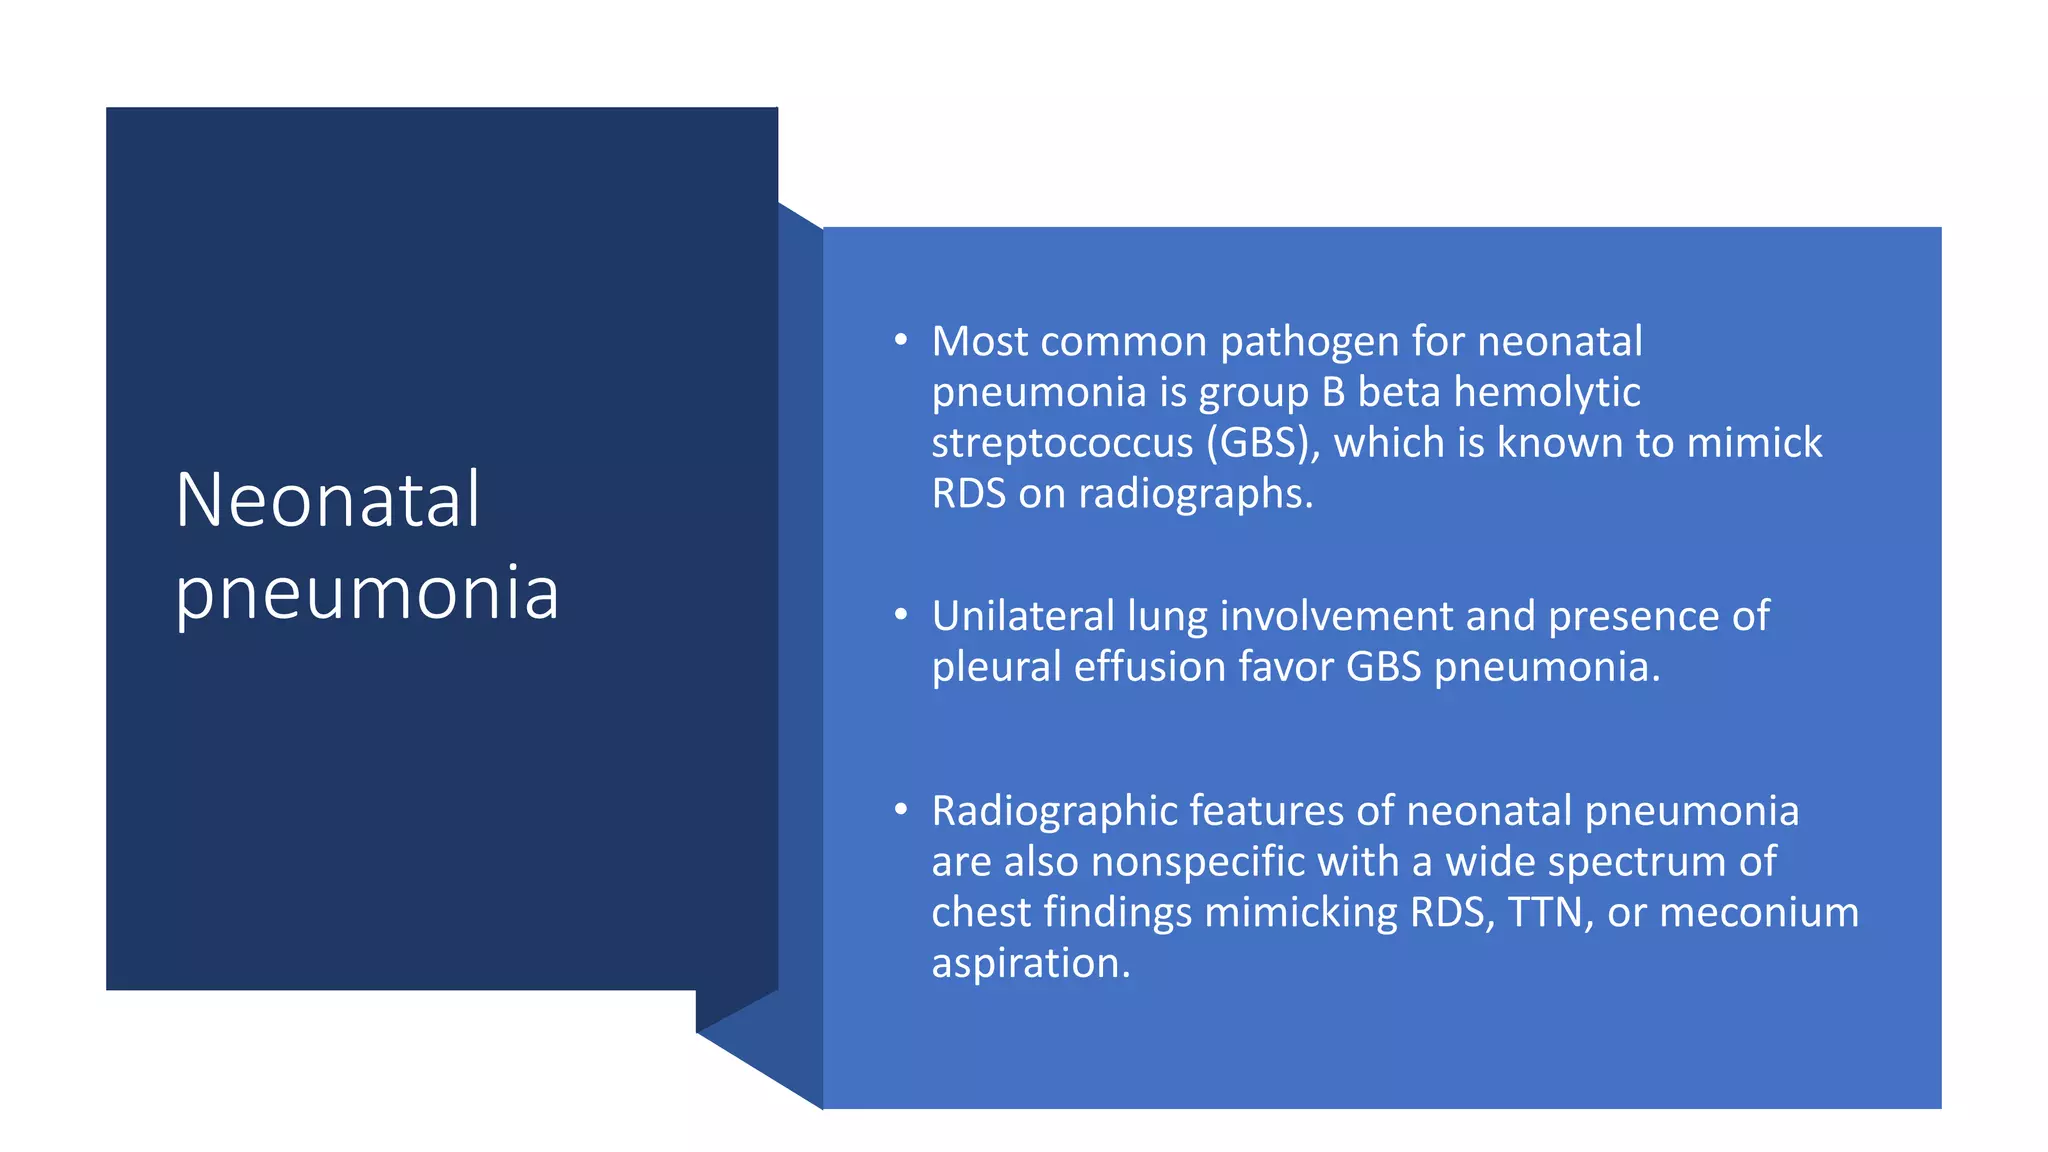

This document provides an overview of neonatal chest x-rays, including when they should and should not be performed, what a normal x-ray looks like, common positions of tubes and catheters, and common causes of respiratory distress in neonates. It discusses the appearance of a normal chest x-ray as well as conditions like respiratory distress syndrome, transient tachypnea of the newborn, meconium aspiration syndrome, and pneumonia. Surgical conditions like diaphragmatic hernia and esophageal atresia are also reviewed.